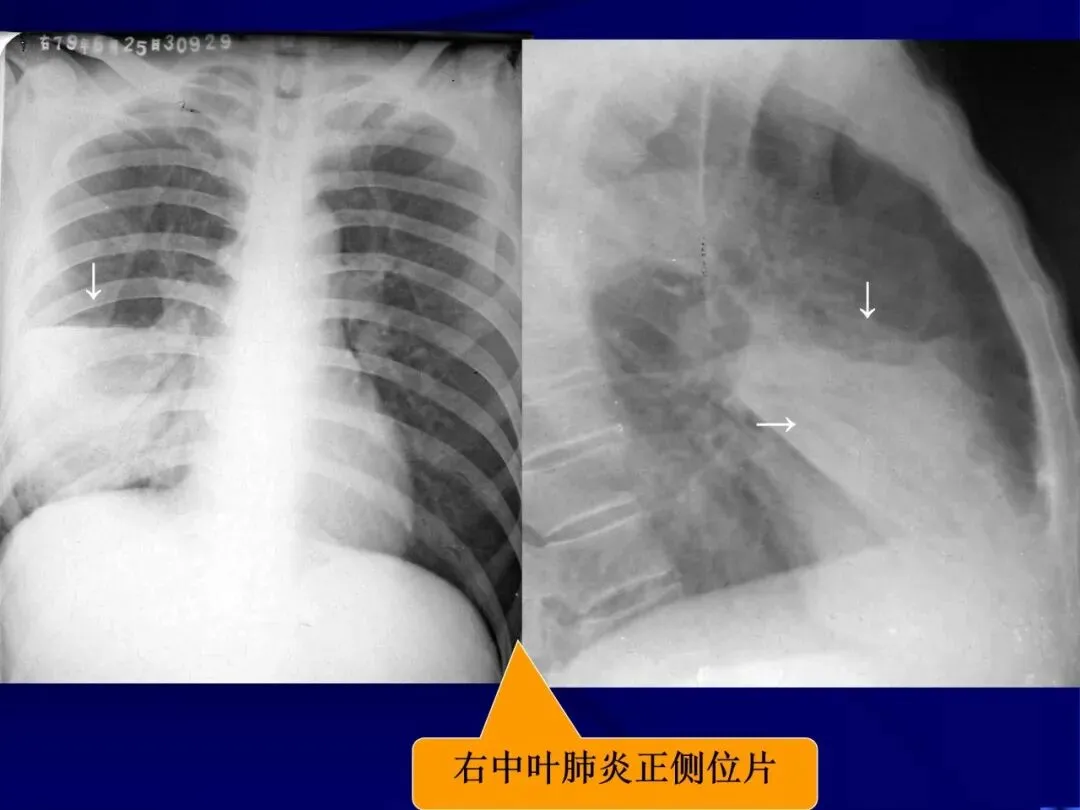

>内科学课件_肺部感染性疾病

内科学课件_肺部感染性疾病